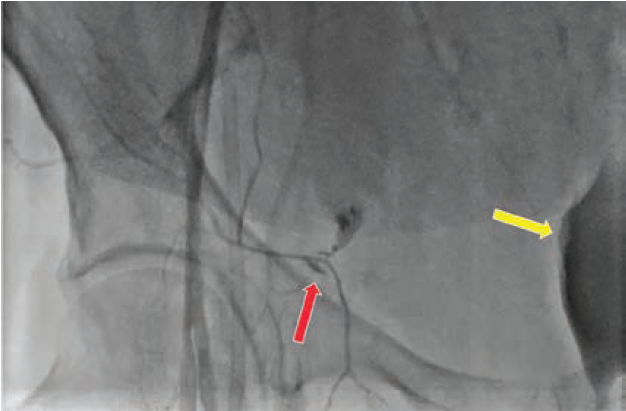

Figure 2 shows an injury to the IE that occurred due to 18-gauge needle laceration, which led to serious retroperitoneal bleeding (note yellow arrow of bladder displaced to the left from massive retroperitoneal bleed) that was only noted after the patient gradually became hypotensive during the case. Figure 3 shows an example of through-and-through sheath insertion of the IE that occurred during venous access that was properly managed with coils that extend distal and proximal to the hole. Of course, it goes without saying that proper access technique with a combination of fluoroscopy AND ultrasound could have prevented these incidents in the first place.

Courtesy of Dr. Curtiss Stinis.